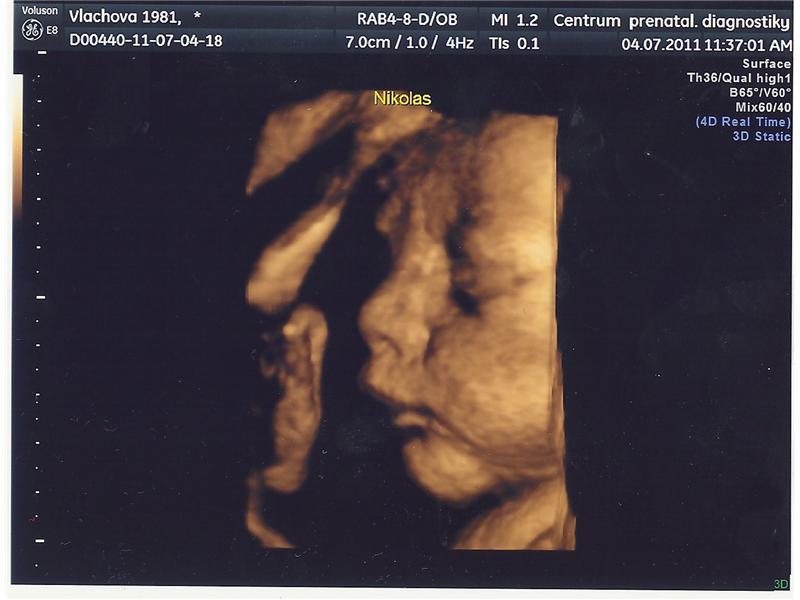

Niky 31+4

3D foto